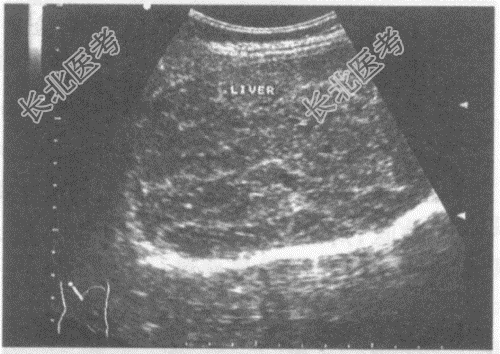

- 单项选择题病史:男性患者, 58岁,自述肝区轻度不适; 一直生活于四川,既往患血吸虫病史13年。

超声综合描述: 肝回声明显不均,全肝布满结节, 呈龟背样改变。

超声提示: A、肝多发占位

B、肝包虫病

C、脂肪肝

D、血吸虫性肝硬化

E、肝脓肿